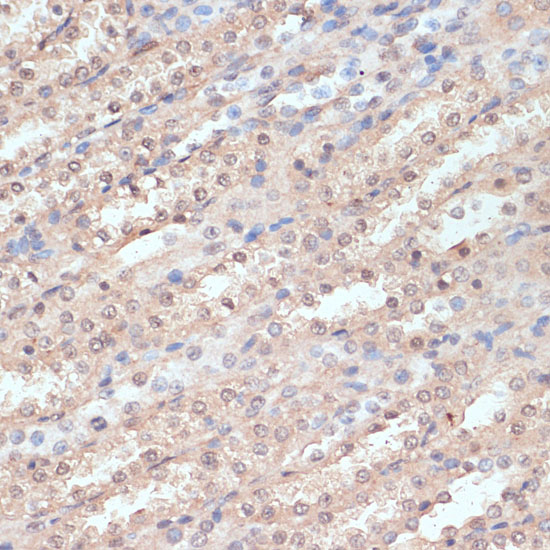

Immunohistochemistry of paraffin-embedded human oophoroma using NAA20 antibody.

IHC 1:50 - 1:200